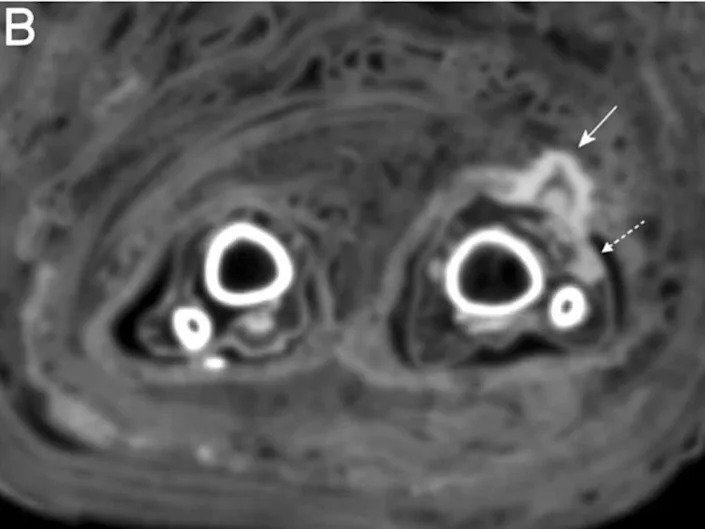

در سیتی اسکن مومیایی پانسمان زخم با «فلش پیوسته» و چرک درون زخم با «فلش مقطع» نشان داده شده است

زینک و همکارانش هنگامی در حال انجام سیتی اسکنهای معمول بر روی مومیاییها بودند، این پانسمان را کشف کردند. سیتی اسکن نشانههایی از وجود چرک را هم در زخم نشان میداد.